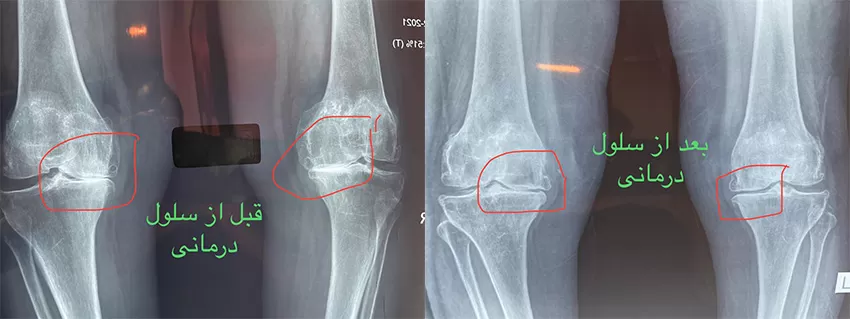

سلولدرمانی زانو؛ بازسازی طبیعی غضروف

سلولدرمانی یکی از جدیدترین روشهای غیرجراحی برای درمان آرتروز زانو بهشمار میرود. در این روش، سلولهای بنیادی از بدن خود فرد استخراج و پس از آمادهسازی، در داخل مفصل تزریق میشوند. این سلولها توانایی ترمیم سلولهای آسیبدیده غضروف و کاهش التهاب دارند.